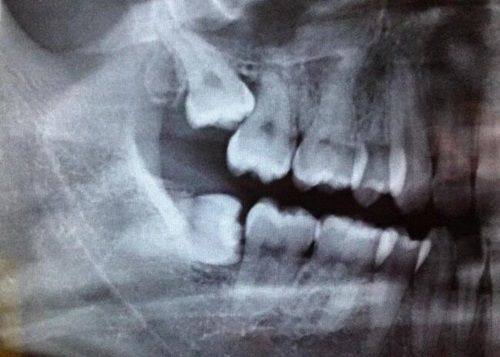

大家在自查咬合时,可以对着镜子观察咬合时上下前牙的位置:如果上牙轻轻盖住下牙的1/3,就是正常咬合;如果下牙盖住了上牙,才需要警惕地包天的问题。如果发现自己或孩子存在地包天的情况,不要拖延,尽早到专精的口腔医疗机构进行检查和干预,不同年龄段的地包天都有对应的至佳矫正方案,早干预不仅可以降低治疗难度,还能节省治疗费用,同时改善面部外观和口腔功能。需要注意的是,不要自行通过网络信息判断病情,一定要由专精的口腔医生通过口腔检查、X光片等手段进行精细诊断,制定个性化的治疗方案,才能获得至佳的矫正成效。无论是儿童还是成人,只要及时采取正确的矫正手段,都可以有效改善地包天问题,修复健康的咬合状态和美观的面部外形。